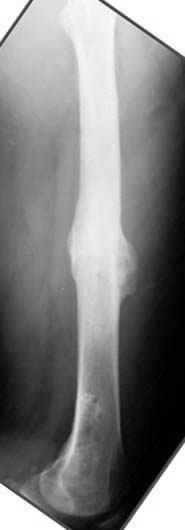

хотя даже если бы и инфекция , то nail exchange с рассверливанием канала - вариант дебрайдмента) Я думаю, что последовательность развития событий:

Узкий к-м канал - тонкий гвоздь- усталостный перелом дистальных винтов - развитие нестабильности и как ее результат остеолиз вокруг гвоздя - деформация анатомической оси бедра. Похоже, что я понял почему аппарат, а не новый гвоздь:-)

Да, но если, скажем, течет из инфицированных каналов запирающих винтов, да инфекция в дистальном метафизе бедра - устанешь сверлить.

Да, наверно. Но если ничего другого нету, ту небольшую деформацию можно было устранить дистрактором одномоментно ввести другой гвоздь.

ЕТ - Изначально костно-мозговой канал бедра был узкий, дальнейшее его рассверливание ещё больше скомпрометирует прочность бедра( латеральный кортекс дистального отломка уже истончен), приведет к дефекту наружной стенки - хотя это только мои догадки - хотелось бы знать мнение Джолдаса о выбранной тактике.